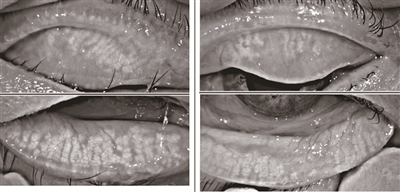

干眼症患者睑板腺重度萎缩,导致油脂分泌减少,泪液快速蒸发出现干眼症状。